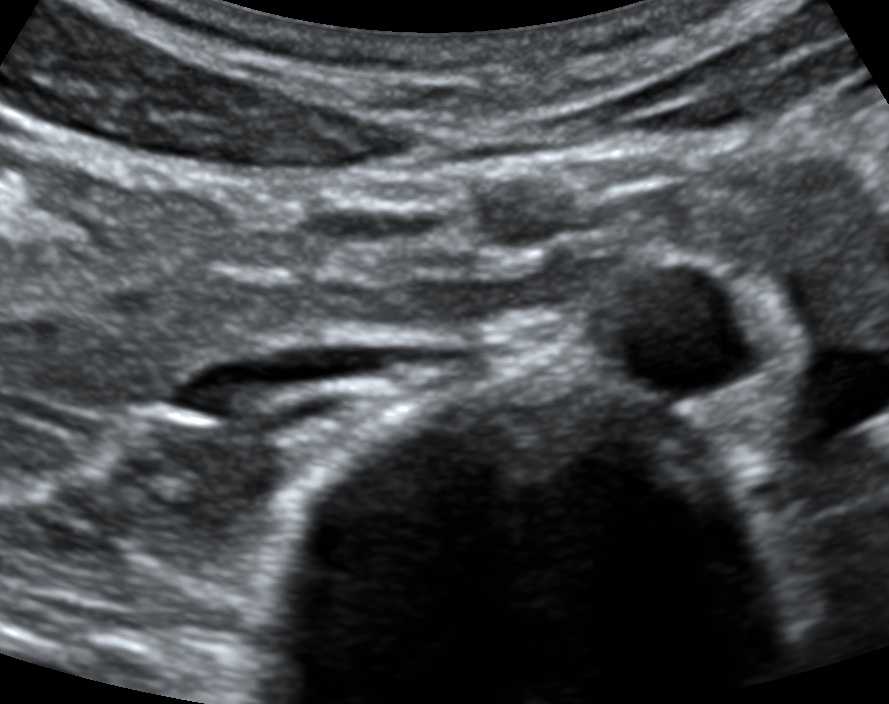

Aortic scan – bifurcation

The aortic scan may be used to detect an abdominal aortic aneurysm (AAA). This scan requires visulatization of the aorta starting from the external landmark of the xiphoid process to the aortic bifurcation into the common iliac vessels. A vessel size of ≥ 3cm at any point constitutes AAA.

The IVC collapses easily with pressure (shown on image left, anatomic right). The aorta remains round with pressure (shown on image right, anatomic left). The vessels lie anterior to the spine, which casts a shadow posteriorly.